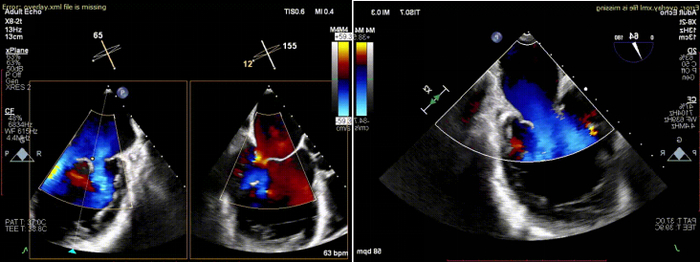

术中全麻成功后,穿刺右股静脉,在超声和射线辅助下成功穿刺房间隔。使用血管鞘相继扩张股静脉后,经超硬导丝导入24F导引鞘并且成功进入左房。在经食道超声辅助下,在2区成功夹闭二尖瓣返流区域,释放2枚二尖瓣瓣膜夹。

术后,患者反流程度从4+转至1+,即刻超声提示二尖瓣返流量下降到轻度,跨二尖瓣平均压差4mmHg。手术操作时间110分钟,透视时间总计为9分钟,手术取得成功。